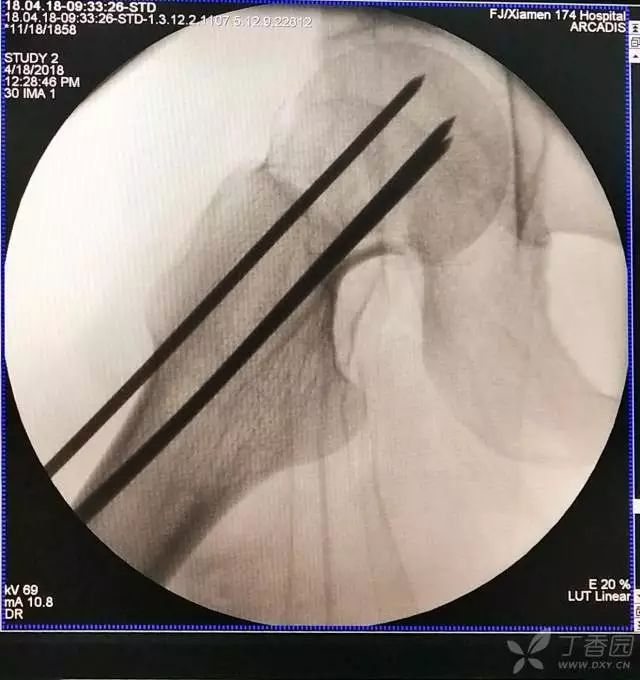

7. 摆 4 字位检查侧位导针的位置是否恰当

8. 最后测深依次拧入合适长度的螺钉